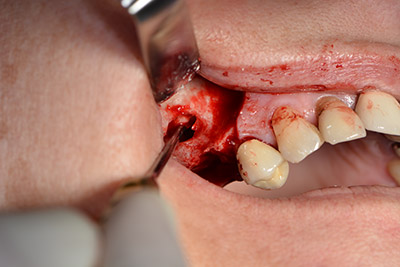

The classic incision (crestal, buccal relief) and the preparation of the mucoperiosteal flap enabled a good overview.

The next step was the sinus floor elevation with simultaneous implantation. The Implantmed also had a presetting at the first position for the buccal fenestration of the maxillary sinus wall.

The fenestration was prepared at 35,000 rpm and then the nasal mucosa were prepared in the cranial direction (Fig. 13 to 14).